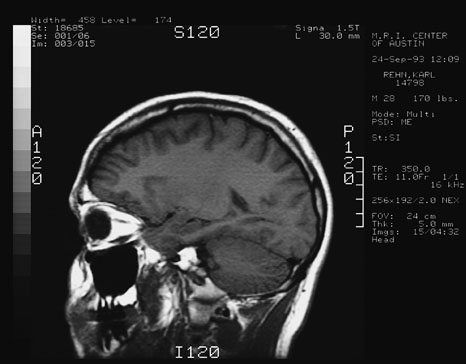

Here are 4 views taken from the MRI of my head.